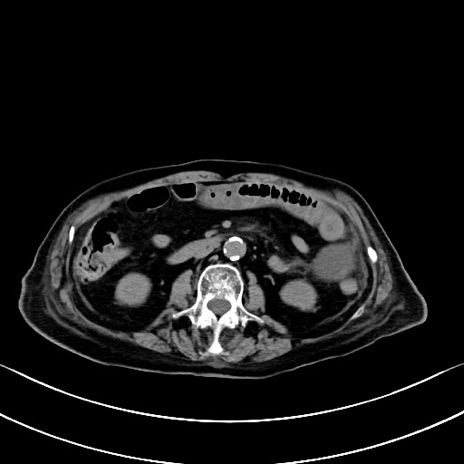

横断像

冠状断像

矢状断像